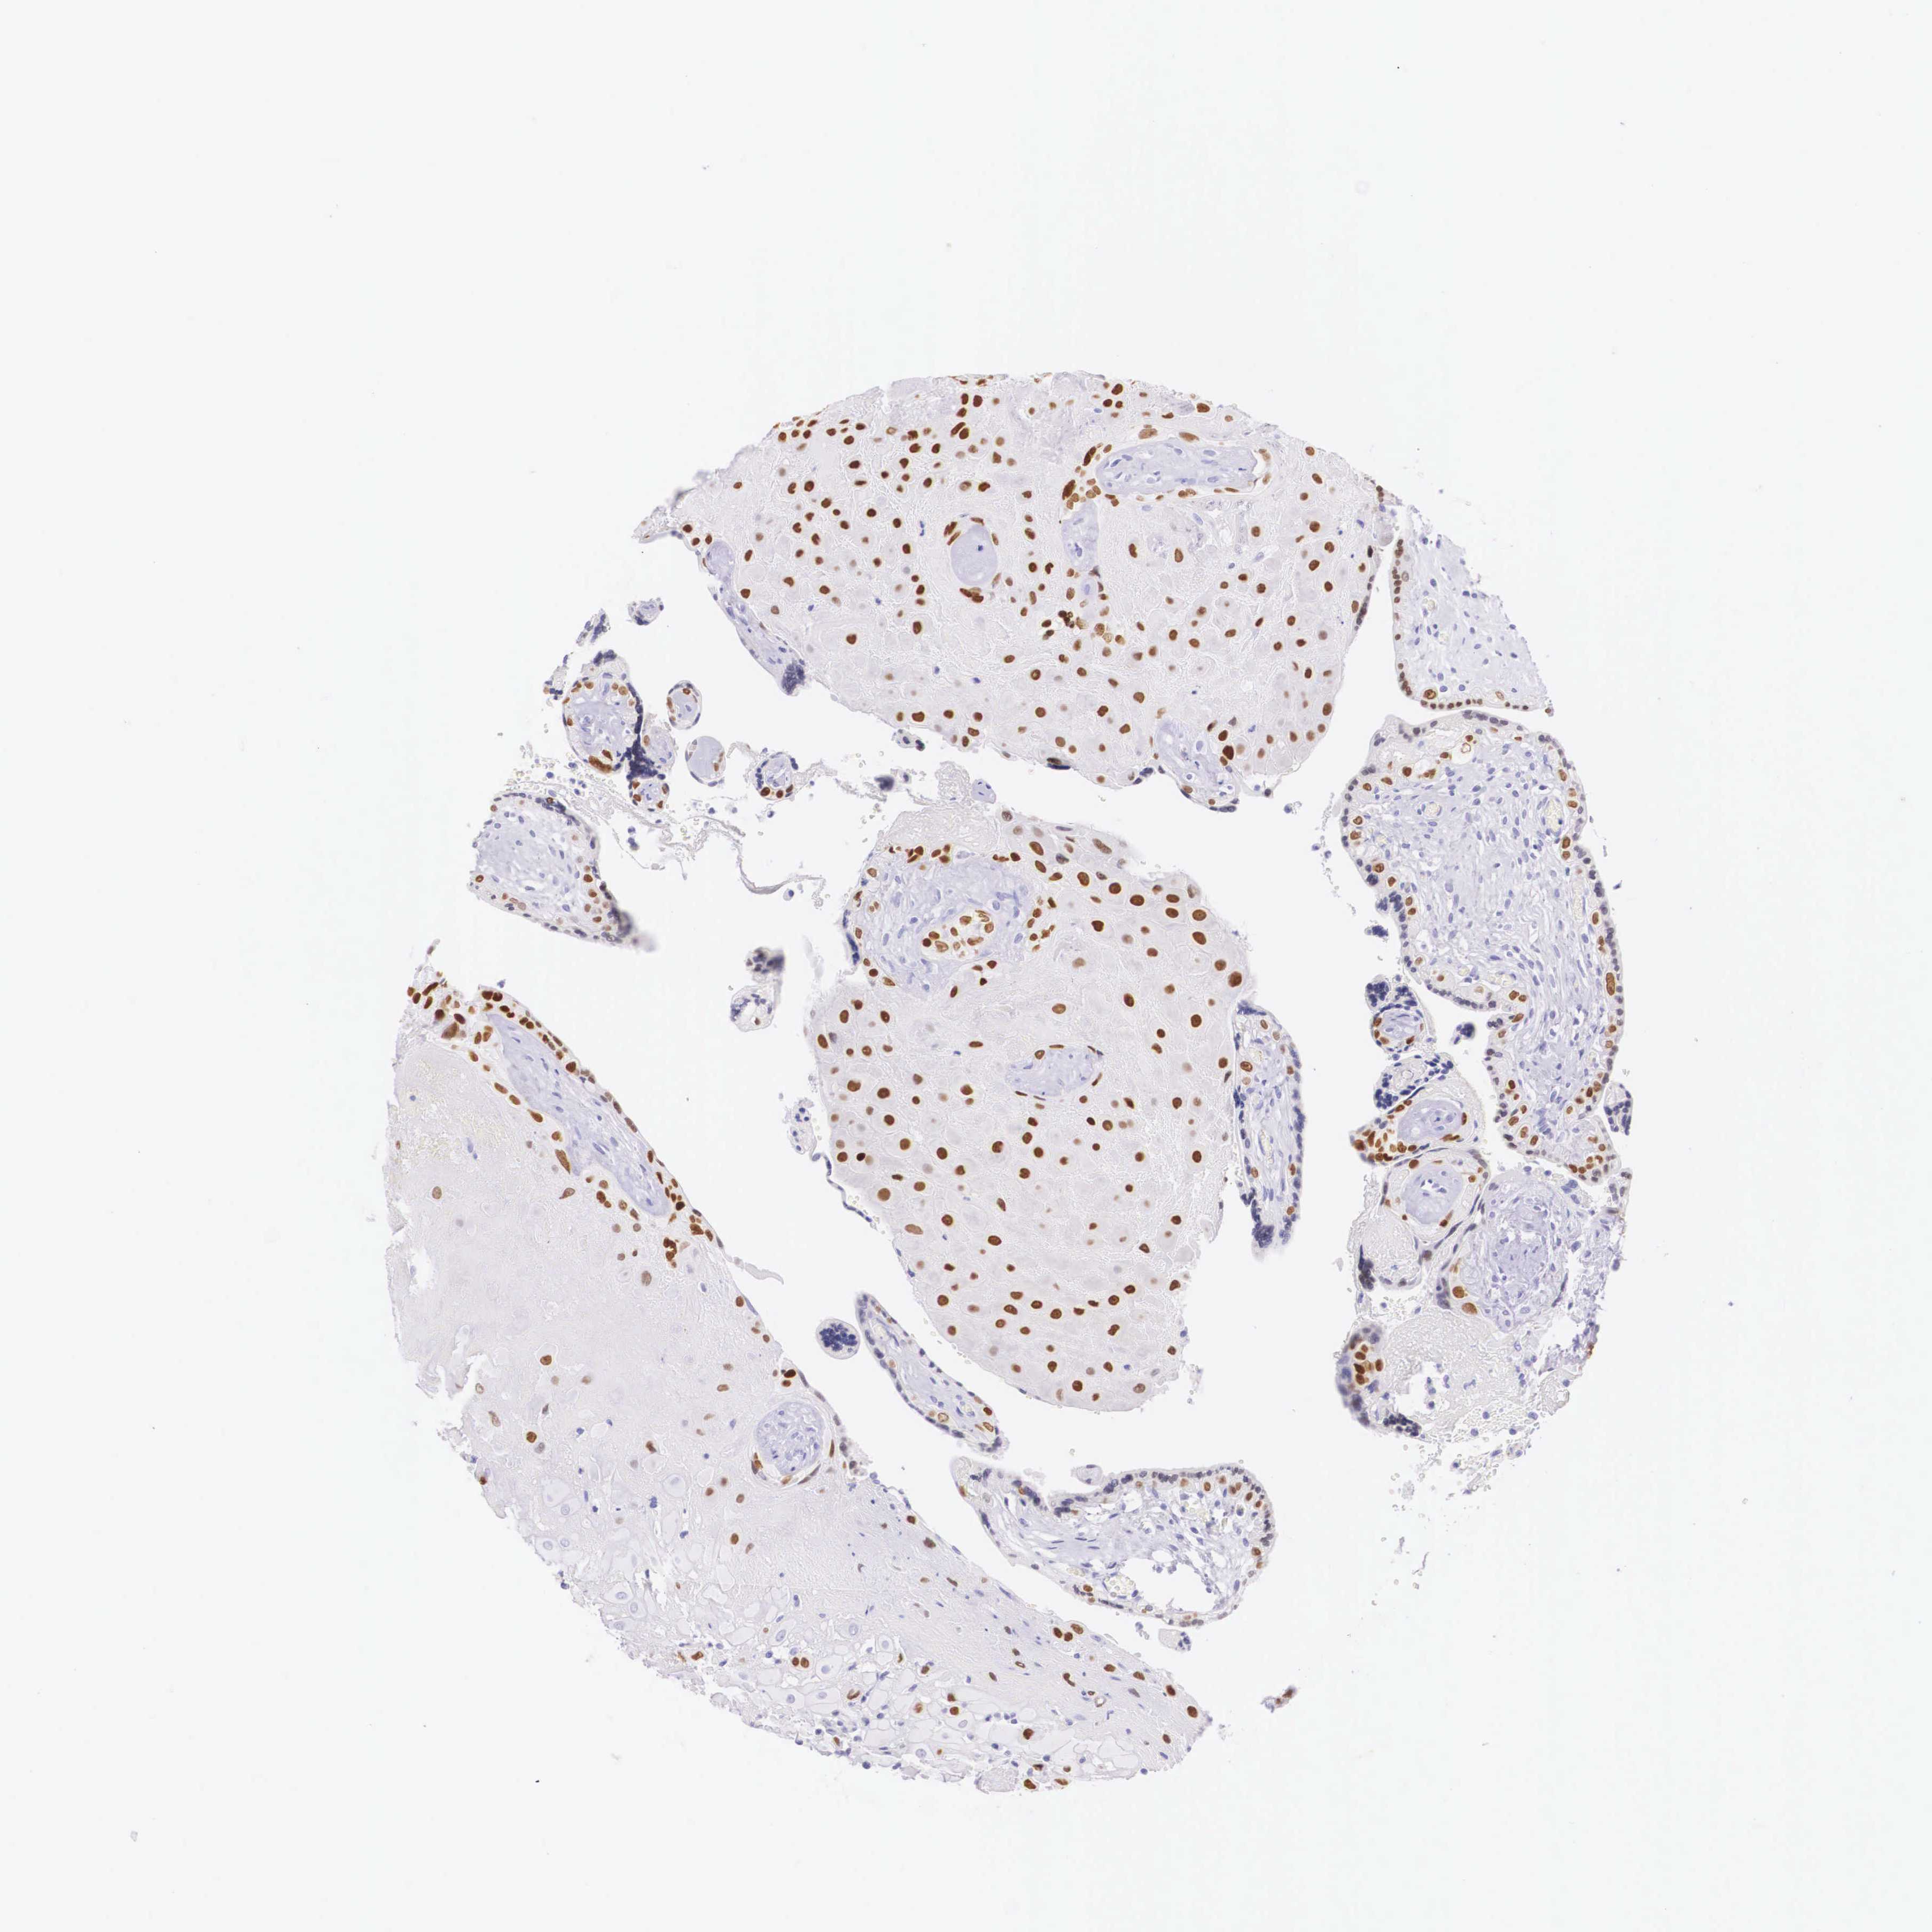

Antibody staining in the annotated cell types in the current human tissue is reported as not detected, low, medium, or high. This score is based on the staining intensity and fraction of stained cells.

Information about each individual sample is listed below, including gender, age, a tissue section image and estimated fractions of cell types. pTPM (transcripts per million) values give a quantification of the gene abundance which is comparable between different genes and samples.

Placenta sample 204 pTPM: 51.4

Cell types%

Trophoblastic cells: 40 Endothelial cells: 35 Other cell types: 25

Female, age 30

Placenta sample 375 pTPM: 39.7